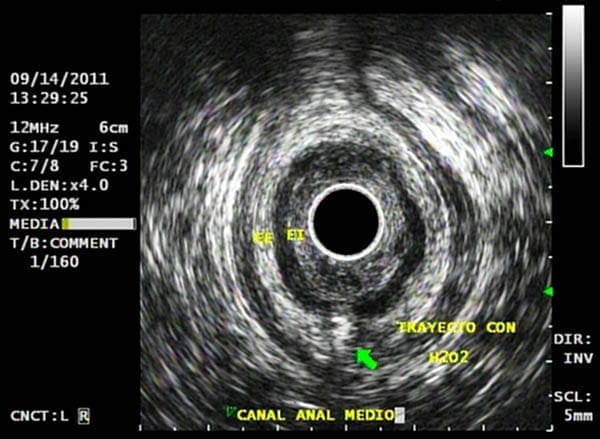

Permite valorar lesiones que pueden estar en el interior del recto, como pólipos o tumores, o en sus paredes, como lesiones de los esfínteres anales y musculatura del suelo pélvico, prolapso rectal, etc., o por fuera de la pared del ano y recto, como inflamaciones (abscesos), fístulas, y otras patologías.